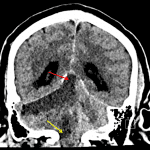

Indication: Follow-up, known occlusion of the right vertebral artery

- Hypodensity and loss of gray-white differentiation in the right cerebellar hemisphere extending into the vermis

- Right cerebellar tonsillar herniation with crowding of the foramen magnum

- Upward transtentorial herniation of the vermis with effacement of the basal cisterns and fourth ventricle

- Dilation of the lateral and third ventricles with associated periventricular hypoattenuation

- Tonsillar and upward transtentorial herniation

Evolving large infarct in the right cerebellar hemisphere extending into the vermis. Associated cytotoxic edema results in right cerebellar tonsillar herniation with crowding of the foramen magnum as well as upward transtentorial herniation of the vermis with effacement of the basal cisterns and fourth ventricle. Dilation of the lateral and third ventricles with associated periventricular hypoattenuation compatible with acute obstructive hydrocephalus with subependymal edema.